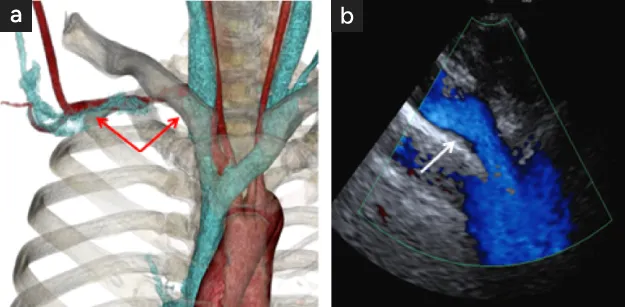

図22

図22. 静脈性教会出口症候群の術前所見

• 造影CTによる右鎖骨下静脈の狭窄・閉塞所見(矢印間)

• 超音波ドプラ血流検査による鎖骨下静脈の狭窄所見(矢印)